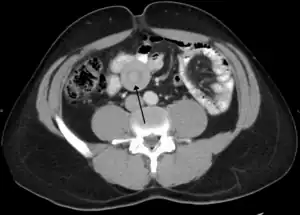

| An intussuception as seen on CT | |

An intussusception is often suspected based on history and physical exam, including observation of Dance's sign. A digital rectal examination is particularly helpful in children, as part of the intussusceptum may be felt by the finger. A definite diagnosis often requires confirmation by diagnostic imaging modalities. Ultrasound is the imaging modality of choice for diagnosis and exclusion of intussusception, due to its high accuracy and lack of radiation. The appearance of target sign (also called "doughnut sign" on a sonograph, usually around 3 cm in diameter, confirms the diagnosis. The image seen on transverse sonography or computed tomography is that of a doughnut shape, created by the hyperechoic central core of bowel and mesentery surrounded by the hypoechoic outer edematous bowel.[8] In longitudinal imaging, intussusception resembles a sandwich.[8] It is also called "pseudokidney" sign because hyperechoic tubular centre is covered by a hypoechoic rim producing a kidney-like appearance.[9]

Axial CT scans of the abdomen showing multiple intussusceptions in the jejunum -

Small intestinal invagination on computed tomography -